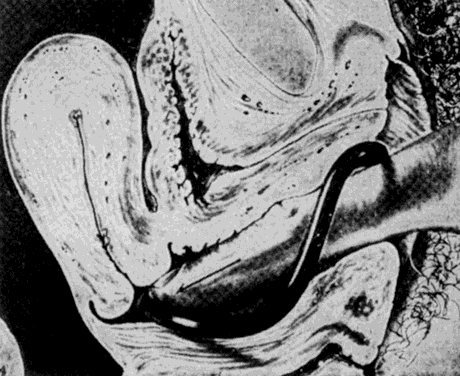

Fig. 7. Lever pessary in place after the uterus has been brought forward; the inner end behind the cervix holding it up and back, and the outer end resting on the muscles of the pelvic floor. Anteriorly it gets its support from the soft tissue between it and the pubic arch.(Crossen RJ: Disease of Women, 10th ed. St. Louis, CV Mosby, 1953)

Fig. 6. Introducing a lever pessary. The index finger is passed to the top of the posterior end, which is then depressed until it can be pushed past the cervix.(Crossen RJ: Disease of Women, 10th ed. St. Louis, CV Mosby, 1953)